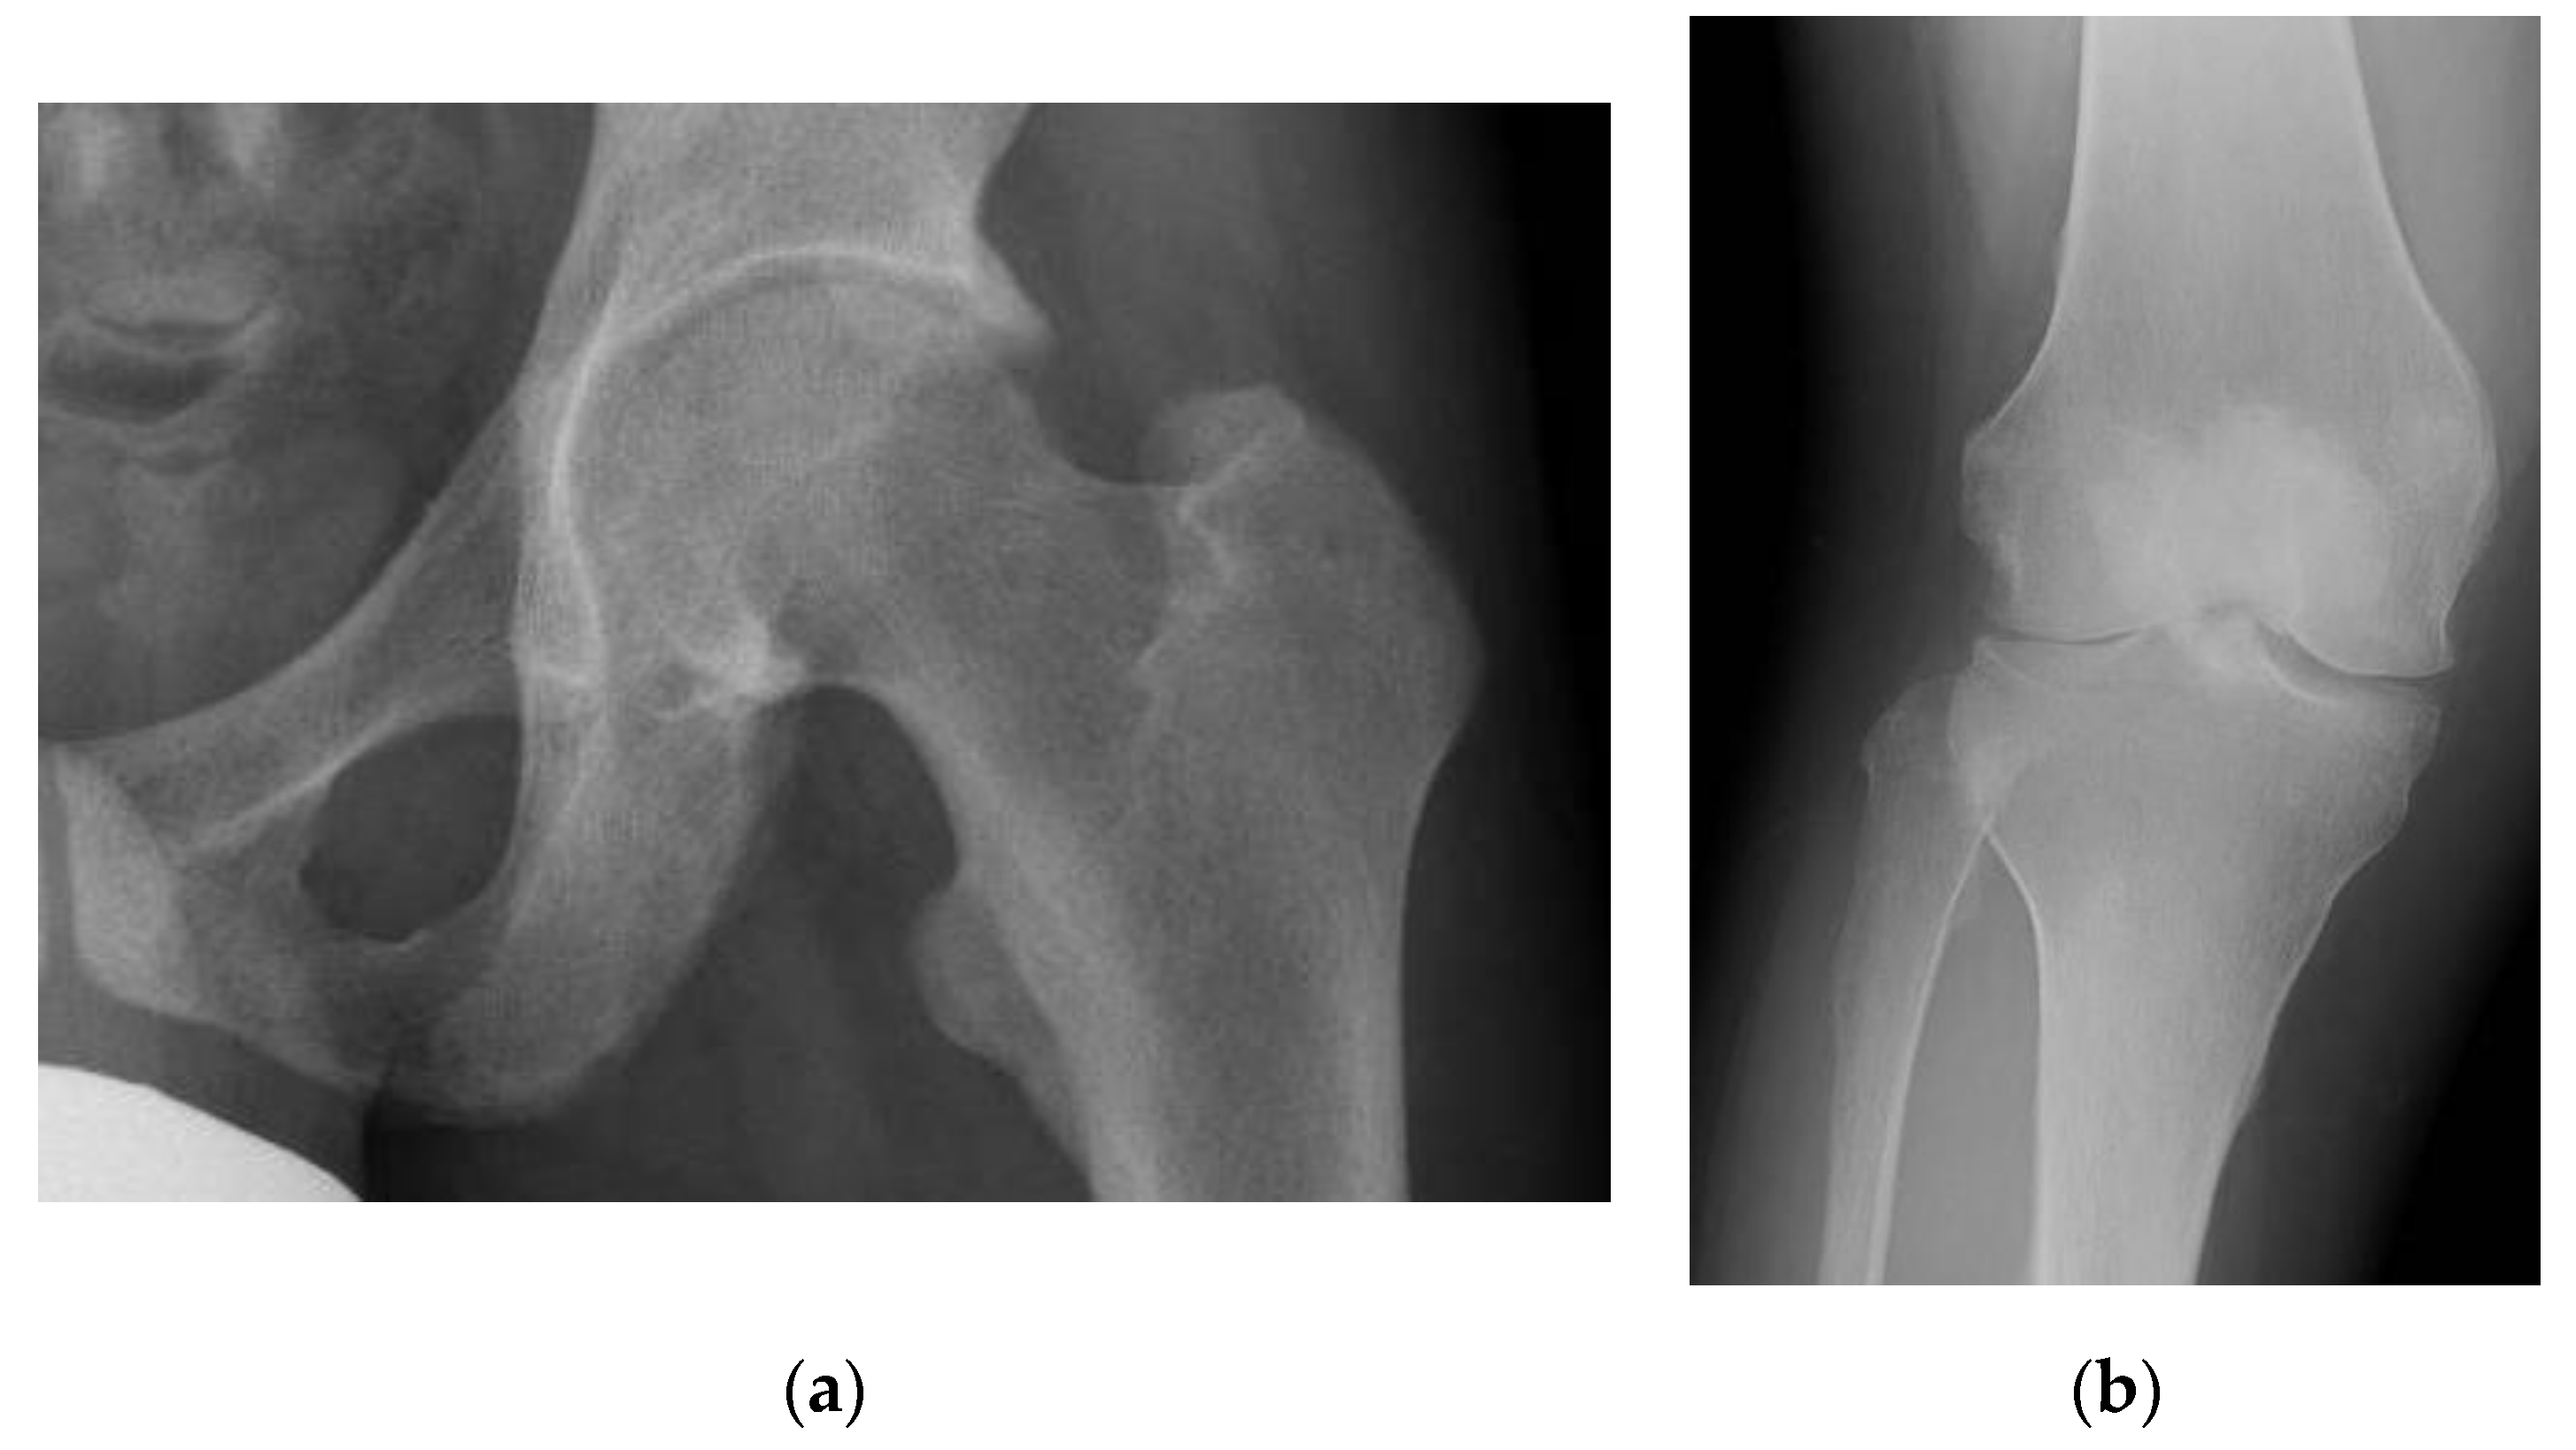

3.1. Pseudofracture and Fracture

3.5. Osteoarthritis